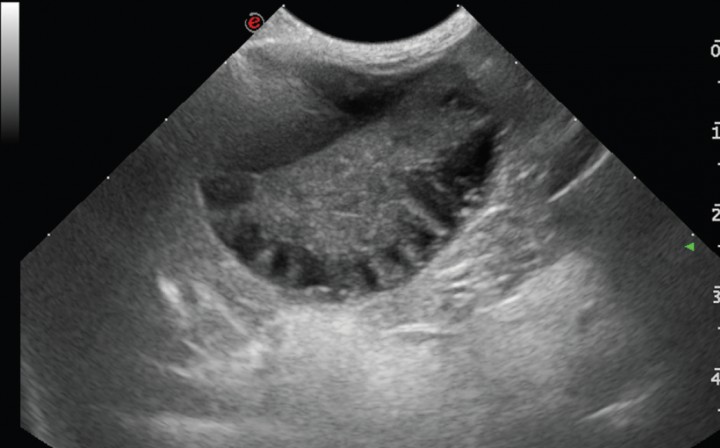

La ecogenicidad del parénquima hepático fue normal en la mayoría de los casos [58,8 % (21/37)], se visualizó hipoecogénico de manera difusa en el 18,9 % (7/37), hiperecogénico en el 13,5 % (5/37) y heterogéneo en el 10,8% (4/37). Se apreció una ligera efusión peritoneal en 4/37 casos (10,8%) y el peritoneo se encontraba aumentado de ecogenicidad en 4/37 casos (10,8 %); los dos casos de rotura de pared biliar (Fig. 9) presentaban ambas alteraciones, correspondiéndose la efusión peritoneal con un exudado.

<p>Imagen ecográfica de la vesícula biliar en corte transversal de un Chihuahua hembra de 5 años que presentaba vómitos, letargia y dolor abdominal. (A) Se visualiza la vesícula biliar aumentada de tamaño, con la pared irregular y engrosada, con contenido ecogénico inmóvil (mucocele biliar de Tipo IV). (B) Además se observaba el peritoneo adyacente hiperecogénico y presencia de líquido libre, siendo el diagnóstico definitivo rotura de la pared de la vesícula biliar y peritonitis focal.</p>

Figura 9

Imagen ecográfica de la vesícula biliar en corte transversal de un Chihuahua hembra de 5 años que presentaba vómitos, letargia y dolor abdominal. (A) Se visualiza la vesícula biliar aumentada de tamaño, con la pared irregular y engrosada, con contenido ecogénico inmóvil (mucocele biliar de Tipo IV). (B) Además se observaba el peritoneo adyacente hiperecogénico y presencia de líquido libre, siendo el diagnóstico definitivo rotura de la pared de la vesícula biliar y peritonitis focal.